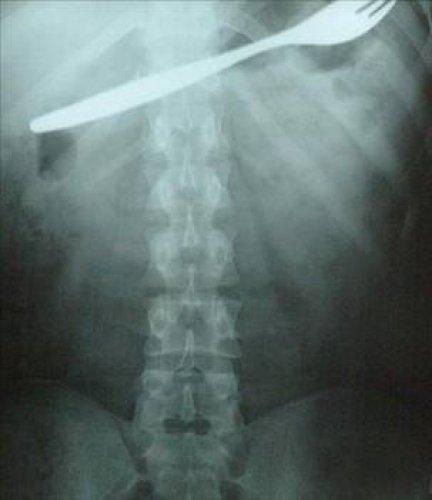

En ilginç tıbbi vakalar 31/39

Kahramanmaraş'ın Afşin ilçesinde bir genç kız, karın ağrısı şikayetiyle gittiği hastanede, midesinde çatal olduğunu öğrenince şok oldu. Genç kızın çatalı küçük yaşta yuttuğu sanılırken, çatal başarılı bir ameliyatla çıkarıldı.